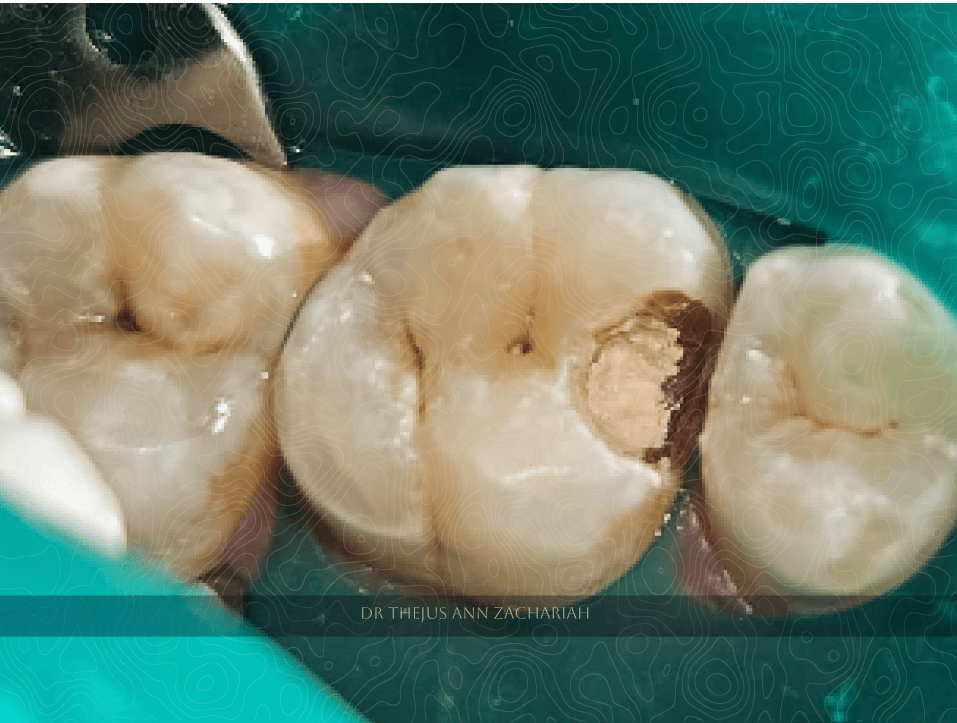

Pin Point Pulp Exposure

alt text